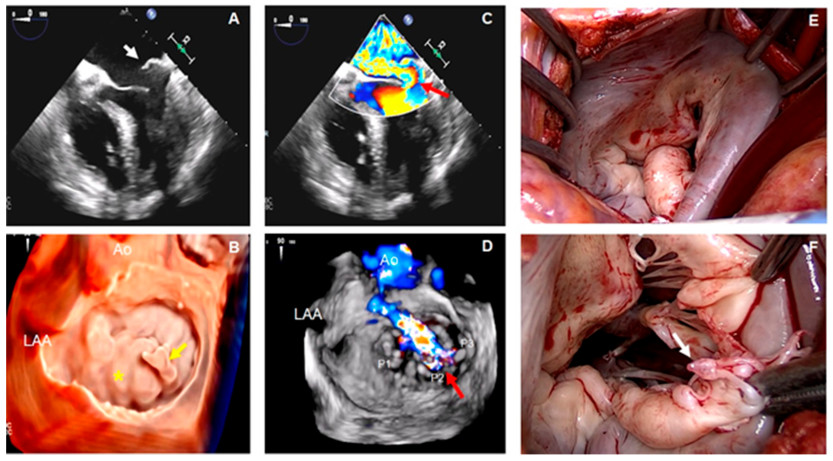

Una mujer de 50 años sin antecedentes médicos acudió al servicio de urgencias por un cuadro de disnea de una semana de evolución. Se sospechó de infarto de miocardio sin elevación del segmento ST , pero en la coronariografía realizada de urgencia no se observó enfermedad coronaria epicárdica significativa. Durante ese mismo procedimiento, en el cateterismo derecho se observó elevación de la presiones de lleno derecha e izquierda e insuficiencia mitral (IM) grave. Debido a la mala ventana acústica del ETT, se realizó un ETE.

En una vista medioesofágica de 4 cámaras se observó que la valva posterior tenía un movimiento ondulante (flail) (Fig. 1A, flecha blanca). En una imagen ampliada D de la VM (vista frontal), se muestra el festón P2 con movimiento ondulante (flail) (Fig. 1B, flecha amarilla) asociado con cambios mixomatosos de los segmentos restantes (Fig. 1B, asterisco amarillo). En la ecografía Doppler color se observa la presencia de un excéntrico de IM grave dirigido hacia adelante (Fig. 1C, flecha roja), y en la ecografía Doppler color 3D correspondiente se identifica el origen exacto del chorro,(jet) entre los festones P2-P3 (Fig. 1D, flecha roja). En concordancia con los hallazgos ecocardiográficos, en los hallazgos quirúrgicos se aprecia el aspecto mixomatoso de la VM (Fig. 1E), así como la rotura de una cuerda tendinosa (Fig. 1F, flecha blanca) correspondiente al segmento P2.

Objetivos de aprendizaje: Estos hallazgos son característicos del espectro degenerativo de la valvulopatía mitral, en el que se han descrito dos fenotipos morfológicos diferentes: degeneración mixomatosa difusa (enfermedad de Barlow) y la deficiencia fibroelástica. (4 La deficiencia fibroelástica se caracteriza por el prolapso de la valva que suele producirse en un segmento aislado, con rotura cordal o valva ondulante (flail). Este segmento suele ser grueso y redundante, mientras que el resto de la valva es delgado y translúcido. (4 Desde una perspectiva ecocardiográfica, es importante medir la altura de las valvas anterior y posterior y el diámetro anular para determinar el tamaño adecuado de la banda o anillo mitral que se debe utilizar. (5 Las vistas frontales de la VM mediante ETE 3D permiten evaluar la protrusión (billowing), el prolapso o el movimiento ondulante (flail) de cualquier segmento de la valva o incluso de las comisuras. (4 Aunque en más del 60% de los pacientes operados se observa prolapso del segmento P2, podría haber otros segmentos concomitantes prolapsados. 2

Algunas de las técnicas de reparación de la VM utilizadas en estos pacientes son la resección de las valvas, la plicatura, las neocuerdas artificiales, la reducción de las valvas y anuloplastia mediante banda o anillo. (5